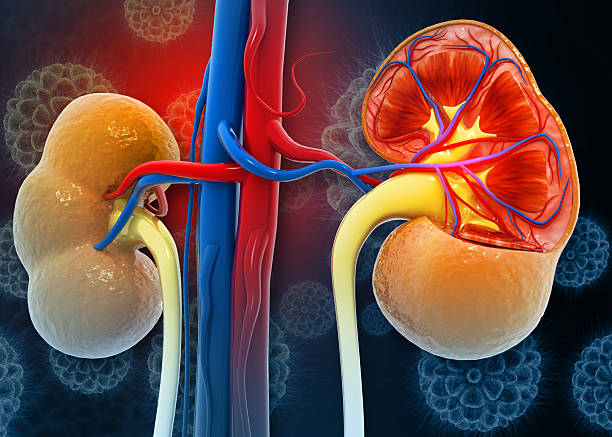

This vitamin supplement may help you heal your kidneys Your kidneys work harder than most people realize. Every minute, they filter toxins, balance fluids, regulate blood pressure, manage electrolytes, and even help produce red blood cells. And yet… we often treat them like unpaid interns — overworked, underappreciated, and ignored until something goes wrong.

Kidneys are metabolically active organs. They process toxins, regulate pH, balance electrolytes, and manage waste — all while being exposed to oxidative stress every single day. This makes them especially vulnerable to free radical damage, inflammation, and gradual cellular breakdown.

Among these nutrients, antioxidants play a central role. Oxidative stress accelerates kidney decline by damaging nephrons (the kidney’s filtering units). Antioxidants neutralize free radicals before they harm kidney cells.

Kidney cells are constantly exposed to oxidative byproducts from filtration and metabolism. Over time, this leads to cellular injury, inflammation, and scarring, which reduces kidney efficiency and accelerates disease progression.

The kidneys operate under constant metabolic stress due to their continuous role in filtering blood, regulating fluid balance, and removing waste products, which exposes them to high levels of oxidative byproducts that can damage cellular structures over time.